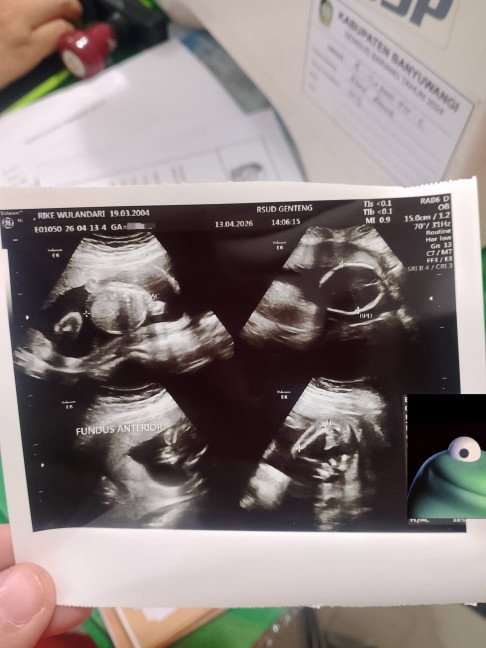

Bun ada yang sama gak Hpht 23 November sampe sekarang belum haid, tapi di tp tuh kadang positif samar kadang negatif, kira² kalo hamil dan USG udah keliatan belum ya?, soalnya mau langsung ke dokter kandungan lumayan jauh, beda kota, jadi mastiin dulu kalo emang harus nunggu kan gak harus bolak balik jadinya 🙏. #mohonbantujawabbunda 🙏